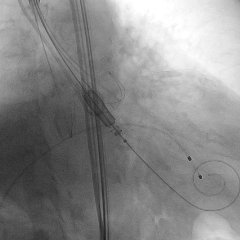

瓣膜释放后造影

双侧股动脉穿刺建立工作路径,送入猪尾导管行主动脉根部造影,交换Safari导丝后将瓣膜输送系统送入升主动脉。输送系统柔顺过弓后顺利将31mm J-VALVE TF瓣膜推至主动脉根部。释放定位件,其可自动定位、轻松准确入窦。定位件入窦后,再次进行造影,在多角度投照下确认瓣膜位置稍高,遂将瓣膜稍向下推,调整至合适位置后将瓣膜释放。瓣膜释放后即刻复查主动脉根部造影,显示瓣膜支架位置稳定、形态展开良好,同轴性佳,未见主动脉瓣反流及瓣周漏,手术顺利结束。瓣膜植入过程仅用时5-10分钟。